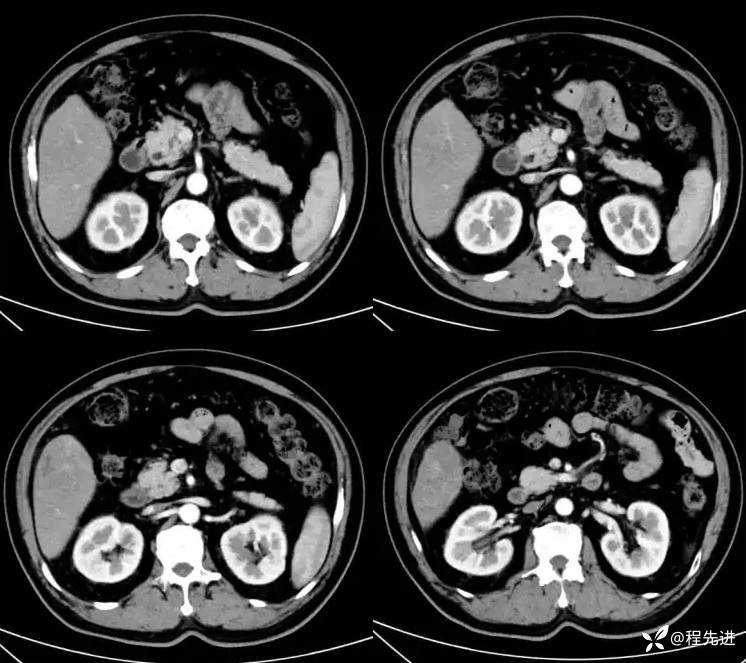

门静脉期:

门静脉期冠状位: